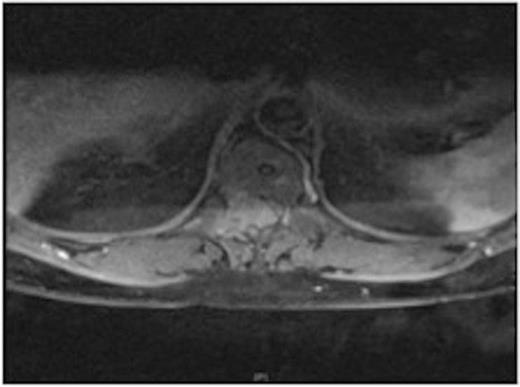

MRI showing the T10-11 extra-dural tumour with erosion of the T12 pedicle

The patient underwent a two-level decompressive thoracic laminectomy and complete macroscopical excision. An intra-operative smear exhibited carcinoid tumour characteristics.